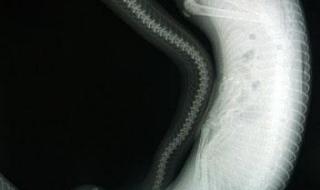

二、北京动物园抓获百米巨蟒是真的吗

1、假的

2、比如网上传的北京动物园百米巨蟒事件,就是假的。还有网传的四川地震惊现55米巨蟒,也是假的。 所以所谓的北京动物园百米巨蟒事件是假的,以及四川55米巨蟒和15米长的“桂花”都是假的,虽然我不敢说这世界上一定没有百米、50米的巨蟒,但网传的北京动物园百米巨蟒以及四川的55米巨蟒肯定都是假的!